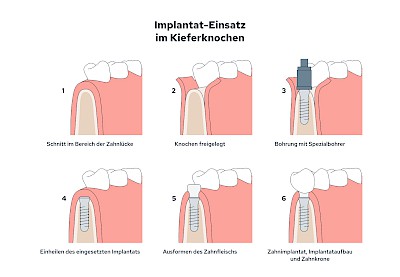

Implantate sind künstliche Zahnwurzeln – meist aus Titanlegierungen, selten auch aus keramischen Werkstoffen. Gehen Zähne verloren werden diese Implantate in den Kiefer eingebracht. Nach einer gewissen Einheilzeit (3-6 Monate) im Knochen wird zunächst für ein bis zwei Wochen das Zahnfleisch im Bereich die Durchtritts-Stelle "geformt" und in der Folge der sogenannte Aufbau (Abutment) aufgeschraubt. Der Aufbau erlaubt dann die Befestigung einer Krone, Brücke oder Zahnprothese.

In seltenen Fällen sind Implantate samt Aufbau aus einem Stück gefertigt. Auch gibt es Situationen, die ein Früh- oder sogar eine Sofortbelastung erlauben - dann kann die Einheilzeit der Implantate in den Knochen verkürzt oder sogar gänzlich darauf verzichtet werden.